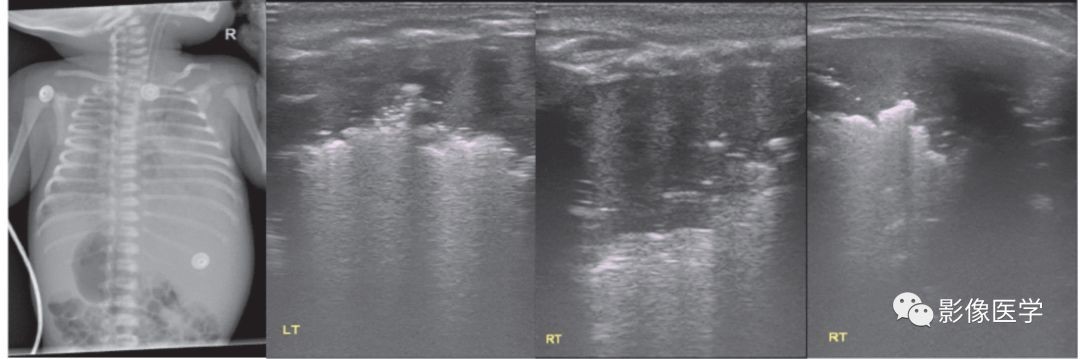

图6-4 重症感染性肺炎(3)

胎龄39周,自然分娩,出生体重3 990g。母产程中发热,体温38.6℃。婴儿出生后即呼吸困难,胸部X线检查显示双肺重症肺炎,透过度显著降低。肺脏超声显示双肺大面积实变,实变区肺组织充气基本消失,提示被累及的肺组织已完全不张,实变区边界不规则。中间两图为探头与肋骨垂直扫描,最右侧为(右侧肺脏)探头与肋骨平行扫描所见。